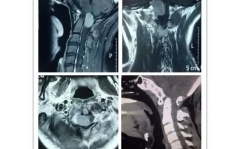

15岁男孩无故腰腿痛“真凶”躲藏三年终现身